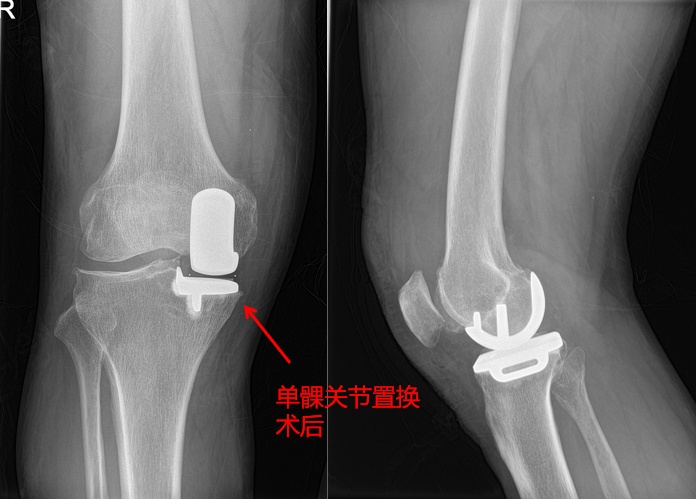

在程飚的主刀下,再加上手术室麻醉医生和护士的精密配合,不到1小时手术便已顺利结束。因单髁关节置换术具有创伤小、出血少、保留原生结构多等优点,术后予以对症治疗和康复锻炼、护理。手术后仅4日,包老先生即能完全负重行走,并且要求出院回家康复。

膝关节单髁置换术针对的是膝关节单间室骨关节炎病患,通过微创手术仅对膝关节病变的内侧或外侧间室表面进行置换,更换病变的软骨面,保留包含前后交叉韧带在内的全部的韧带组织,和其余间室关节软骨,从而实现术后的快速康复,做到更加“精准化”“微创化”。

手术只切除单侧病变的关节面,保留大部分骨质,骨量保存多;

保留前后交叉韧带,完好保留另一侧间室的半月板和软骨,最大限度的保留患者膝关节的本体感觉和关节功能;

植入异物少(包括金属、聚乙烯、骨水泥);

切口小、出血少、疼痛轻,手术创伤和并发症少,配合完善的康复锻炼,术后恢复更快,住院时间更短;